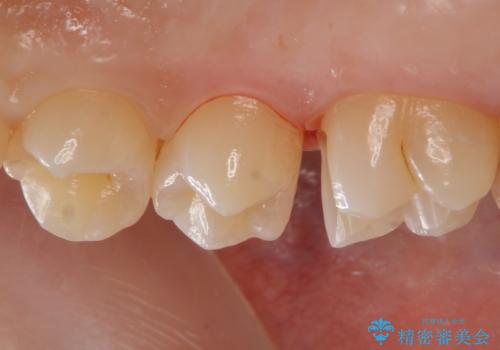

歯と歯の間の虫歯 セラミックインレーでの治療

歯と歯の間に虫歯があったためセラミックインレーで治療をしていきました。

- 右上6 セラミックインレー 77,000円費用は治療当時の料金となります

歯と歯の間は虫歯の好発部位となっています。

今後の虫歯リスクを抑えるためにも適合の良い補綴物を装着することは有効です。